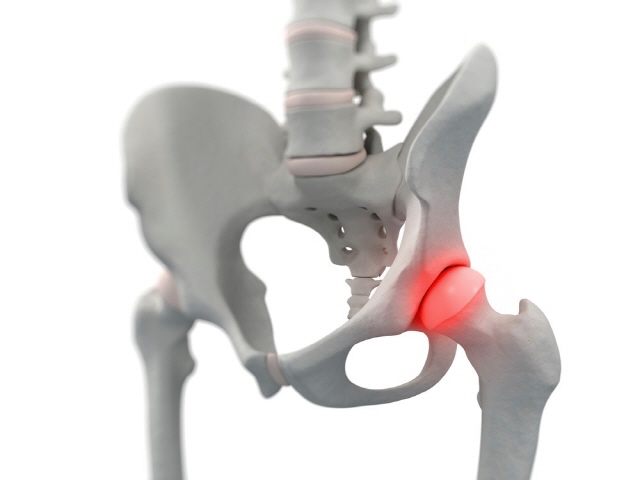

고관절은 엉덩이관절이라고도 불리우며, 보통 알고있는 골반위치에 있고, 공처럼 둥글게 생긴 대퇴골두가 글러브가 감싼듯한 모양으로 비구에 맞물려 있어요.

이렇듯 고관절은 오목하게 들어간 비구와 둥근 공모양의 대퇴골두로 이루어져 있으며 골반과 다리를 이어주는 우리 몸의 핵심 관절인데요. 그리고 고관절은 골반을 통해 전달되는 체중을 지탱해주고 걷기와 달리기같은 다리 운동들을 가능하게 해주는 관절이기도 해요.